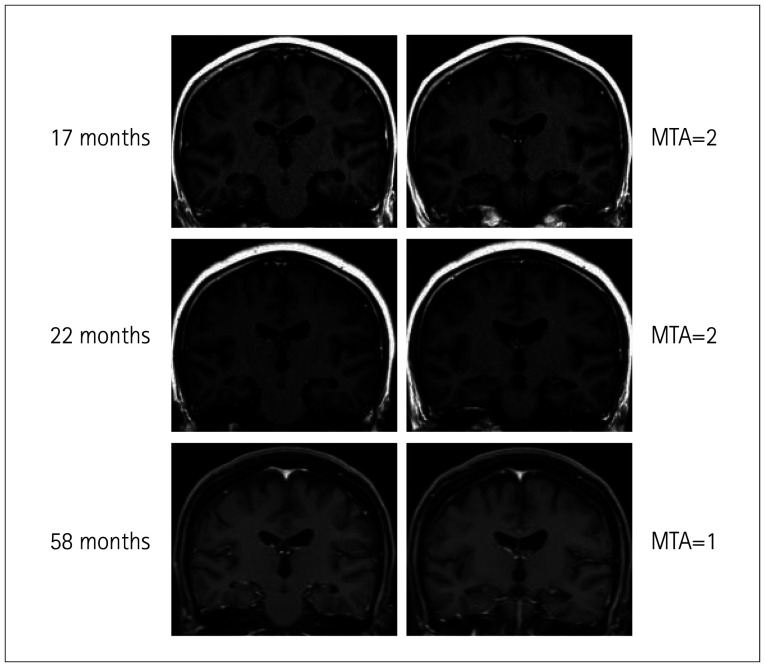

背景与目的:比较伴有和不伴有脑萎缩的抗n -甲基- d -天冬氨酸受体(anti-NMDAR)脑炎患者的临床和实验室特征。方法:对82例抗nmdar脑炎患者采用颞叶中位萎缩(MTA)和脑皮质整体萎缩(GCA)评分评价脑萎缩程度。结果:GCA(+)组癫痫持续状态发生率(pp=0.031)、脓毒症发生率(pp=0.001)高于GCA(-)组。MTA(+)组记忆问题发生率高于MTA(-)组(pp=0.002)。GCA(+)组和MTA(+)组的最大修正Rankin量表(mRS)评分(pp=0.002)和1年mRS评分(pp=0.004)均高于GCA(-)组和MTA(-)组。多元线性回归分析发现,GCA(+)组住院时间较长,治疗反应有限的病例比例较大(均pp=0.005)是发病后1年mRS评分的重要预测因素。结论:MTA和GCA可能与抗nmdar脑炎的严重程度和预后有关。

Methods: Assess cerebral atrophy using median temporal lobe atrophy (MTA) and global cortical atrophy (GCA) scores in 82 anti-NMDAR encephalitis cases.

Results: GCA (+) cases had higher proportions of status epilepticus (p<0.001), memory problems (p=0.031), sepsis (p<0.001), and mechanical ventilation need (p=0.001) than GCA (-) cases. MTA (+) cases had higher memory problems (p<0.001) and sepsis (p=0.002) than MTA (-) cases. GCA (+) and MTA (+) groups had higher max modified Rankin Scale (mRS) (p<0.001, p=0.002) and 1-year mRS (p<0.001, p=0.004) scores than GCA (-) and MTA (-) groups. GCA (+) group had a longer hospital stay and a larger proportion of cases with limited treatment response (both p<0.001) than the GCA (-) group. GCA (p=0.005) was found to be a significant predictive factor for the mRS score 1 year after onset in multiple linear regression analysis.

Conclusions: MTA and GCA may be associated with severity and prognosis in anti-NMDAR encephalitis.